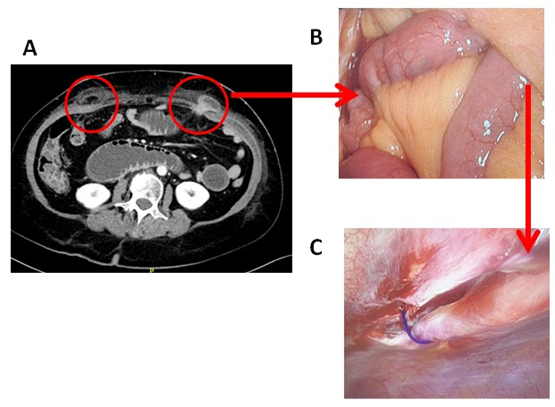

Figure 2: CT scan demonstrating two trocar site hernias demonstrating: A) right upper abdominal quadrant, and left upper abdominal quadrant with Richter´s small bowel hernia B) Intraoperative finding demonstrating small bowel obstruction and C) Closure of the trocar site hernia.

Left upper quadrant (Figure 2) |

12mm |

Bowel obstruction |

Bowel reduction |